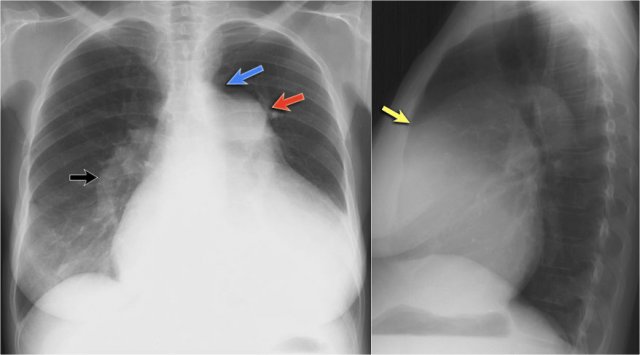

1. No silhouette sign in a consolidation located in the left lower lobe (blue arrow). 2. Silhouette sign in a consolidation in the lingula lobe (yellow arrow). 1. No silhouette sign in a consolidation located in the left lower lobe (blue arrow). 2. Silhouette sign in a consolidation in the lingula lobe (yellow arrow).

Silhouette sign

The silhouette sign refers to the loss of the normal border between structures of different radiographic densities, most commonly air-filled lung adjacent to soft tissue structures like the heart or diaphragm.

This sign is crucial for detecting subtle pathology and localizing lesions within the thorax.

Illustration of the Silhouette Sign

1. No Silhouette Sign (Blue Arrow)

• The left ventricle, located anteriorly, is normally bordered by air-filled lingula of the left upper lobe.

• If a consolidation occurs in the left lower lobe (posterior), the interface between the lingula and the heart remains intact, and the left heart border is preserved.

2. Positive Silhouette Sign (Yellow Arrow)

• When consolidation is present in the lingula, which directly abuts the left heart border, the silhouette of the left ventricle becomes obscured.

• This indicates the pathology is located anteriorly in the chest.

Silhouette Sign – Examples

Case 1: PA View

• The left heart border is obscured on the PA radiograph.

• Without even reviewing the lateral view, this finding localizes the pathology to the anterior segment of the left lung, likely the lingula.

• Diagnosis: Lobar pneumonia due to Streptococcus pneumoniae.

Case 2: PA View

• A consolidation is visible in the left lower lobe (yellow arrow).

• The left heart border remains well-defined with a normal silhouette (blue arrow), indicating the lesion is posterior, not involving the lingula.